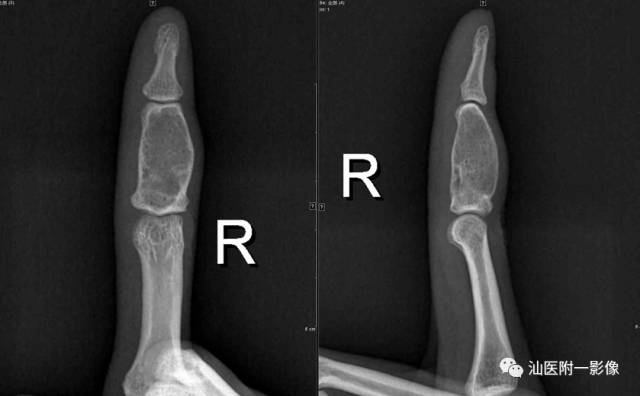

2.内生软骨瘤

•常见的良性骨肿瘤(10%),手短管状骨最为常见的肿瘤。常见于11-30岁。

•内生软骨瘤(骨中央);骨膜/皮质旁软骨瘤(皮质)

•好发于手短管状骨,长骨干骺端/骨干。

•病理:软骨细胞+软骨基质。